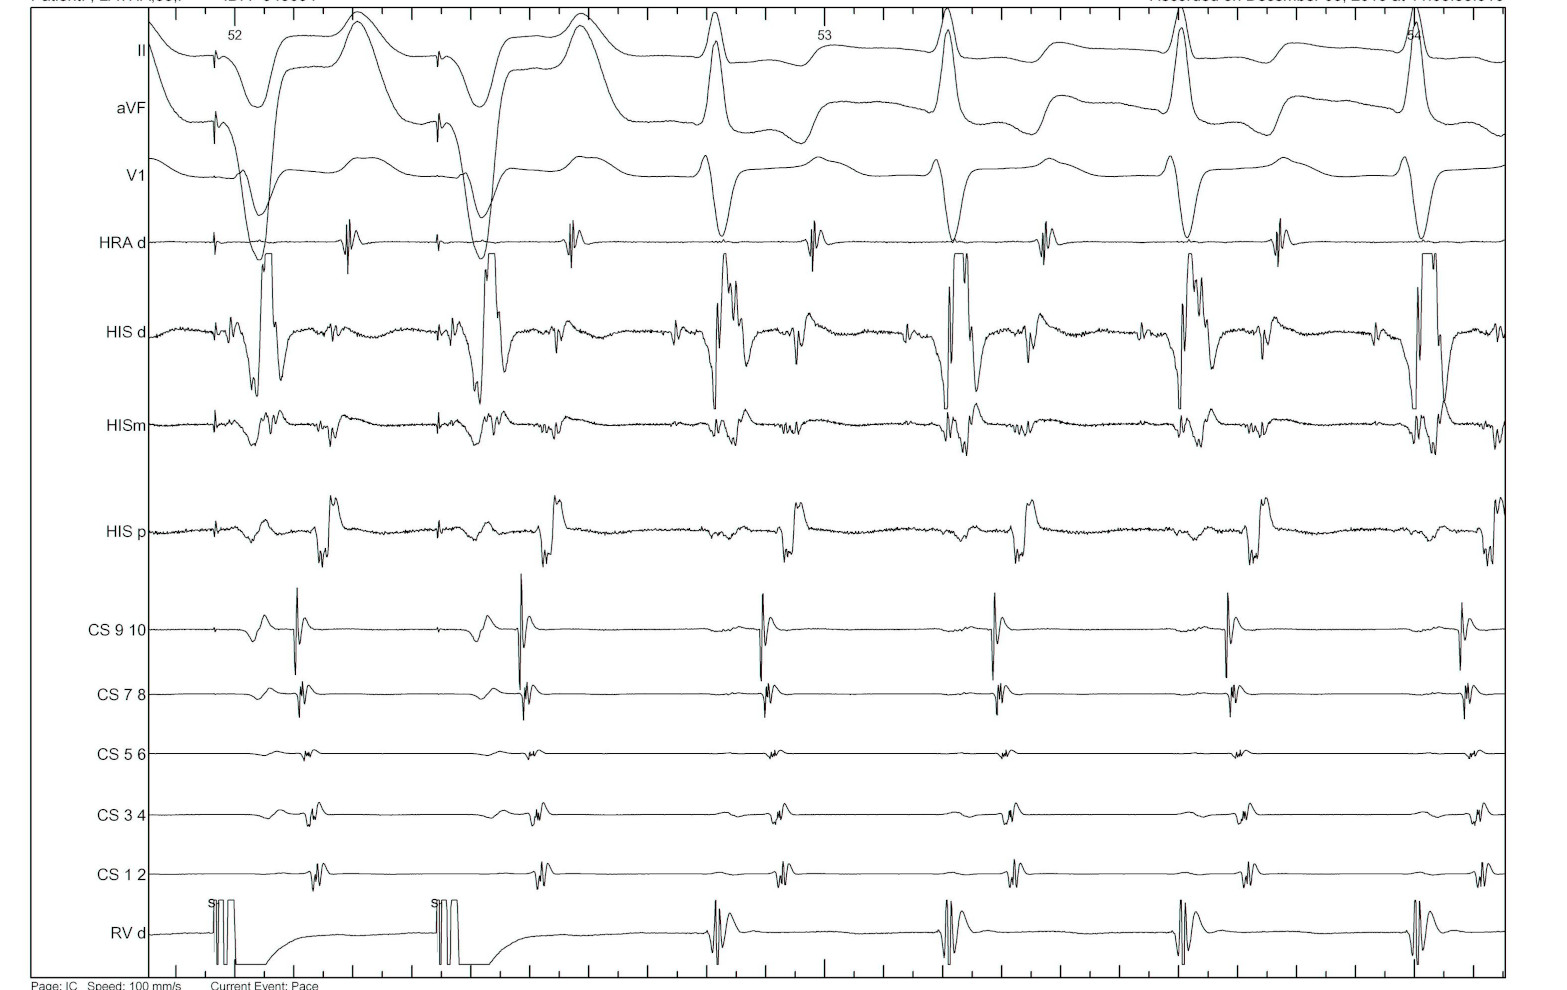

AVRT or AVNRT ? - cPPI-TCL

vav_avrt.jpg

SA-VA